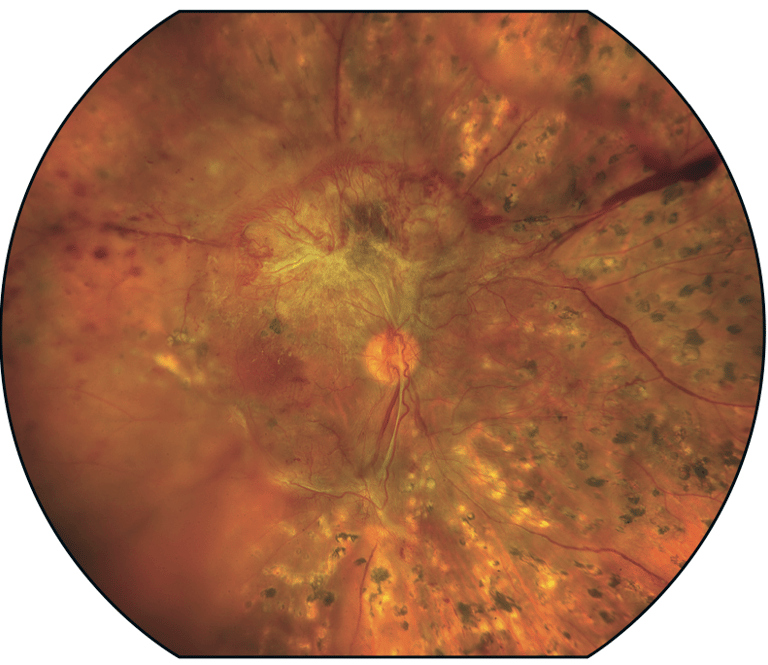

Com o tempo, o excesso de açúcar no sangue pode bloquear os pequenos vasos sanguíneos que nutrem a retina, cortando o suprimento de sangue. Como resultado, o olho tenta criar novos vasos sanguíneos, mas esses novos vasos não se desenvolvem adequadamente e podem vazar facilmente.

Retinopatia diabética inicial: Nesta forma mais comum — chamada retinopatia diabética não proliferativa (RDNP) — novos vasos sanguíneos não estão crescendo (proliferando).

Quando você tem retinopatia diabética não proliferativa (RDNP), as paredes dos vasos sanguíneos da retina enfraquecem. Pequenas saliências se projetam das paredes dos vasos menores, às vezes vazando fluido e sangue para a retina. Vasos retinais maiores podem começar a dilatar e se tornar irregulares em diâmetro. A RDNP pode progredir de leve a grave à medida que mais vasos sanguíneos ficam bloqueados.

Às vezes, o dano aos vasos sanguíneos da retina leva ao acúmulo de líquido (edema) na porção central (mácula) da retina. Se o edema macular diminuir a visão, o tratamento é necessário para evitar a perda permanente da visão.

Retinopatia diabética avançada: A retinopatia diabética pode progredir para esse tipo mais grave, conhecido como retinopatia diabética proliferativa. Nesse tipo, os vasos sanguíneos danificados se fecham, causando o crescimento de novos vasos sanguíneos anormais na retina. Esses novos vasos sanguíneos são frágeis e podem vazar para a substância gelatinosa e transparente que preenche o centro do olho (vítreo).

Na própria consulta, após a dilatação da pupila é realizado um mapeamento da retina, para diagnóstico da retinopatia diabética. Outros exames adicionais podem ser necessários, como a angiografia com fluoresceína e a tomografia de coerência óptica (OCT).